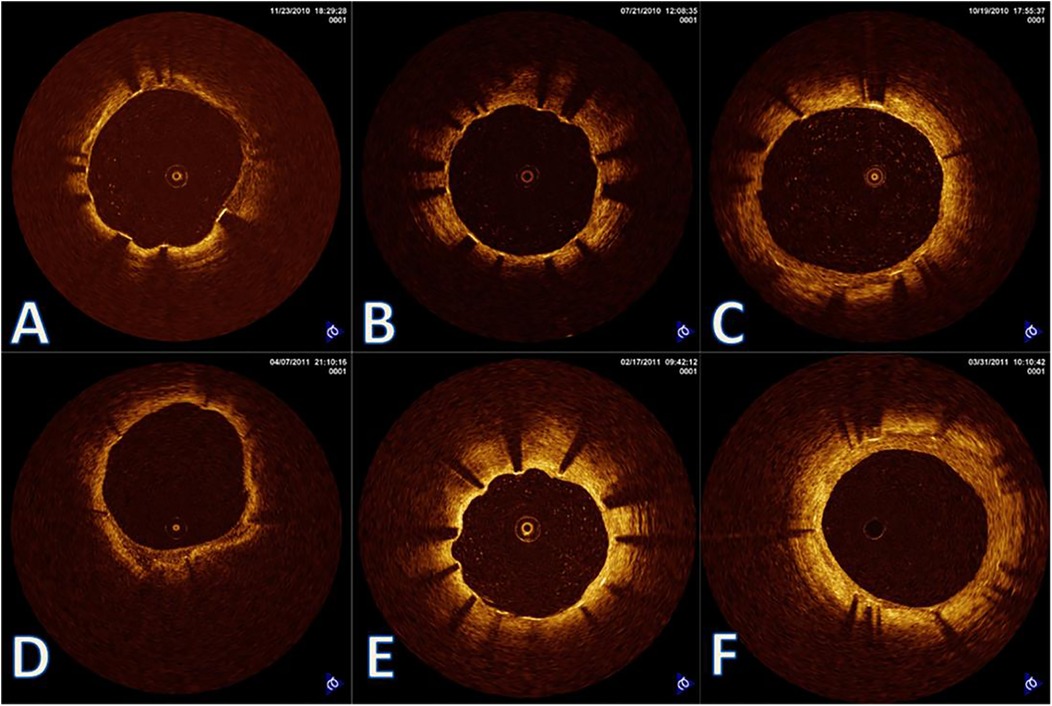

Background: Biological aging and prolonged cold exposure each impair vascular healing after implantation of a drug-eluting stent. However, their combined effect—particularly in older adults living in cold climates—remains poorly understood. Objective: To evaluate the joint impact of aging and cold exposure on vascular healing and their association with major adverse cardiovascular events (MACEs) after sirolimus-eluting stent implantation. Methods: In this retrospective cohort study, 119 patients were stratified into three age groups (≤55, 56–65, and >65 years). Vascular healing was assessed using serial optical coherence tomography (OCT) at 6 and 12 months, with a focus on strut coverage, neointimal hyperplasia (NIH), and spatial heterogeneity. Cold exposure was quantified with the validated Cold Exposure Diary Questionnaire and corroborated by regional meteorological data. The primary end point was the incidence of MACEs at 12 months. Results: OCT showed delayed endothelialization at 6 months in patients above 65 years compared to younger cohorts (uncovered struts, 11.7% vs. 6.1%; P < 0.001), along with accelerated late-phase NIH progression (3.33 vs. 1.67 μm/month; P < 0.001). Prolonged cold exposure (>12 h/day) was independently associated with greater neointimal heterogeneity (P=0.003) and a higher risk of MACEs (hazard ratio, 3.42; 95% CI, 1.65–7.11). A 4D Risk Score, combining OCT-derived healing metrics and cold-exposure data, predicted MACEs; however, external validation is required. Conclusions: In older patients, the interaction between aging and prolonged cold exposure results in biphasic vascular healing, characterized by early delayed endothelialization followed by excessive neointimal proliferation. The proposed 4-D Risk Score may facilitate individualized risk stratification after percutaneous coronary intervention and warrants prospective validation.